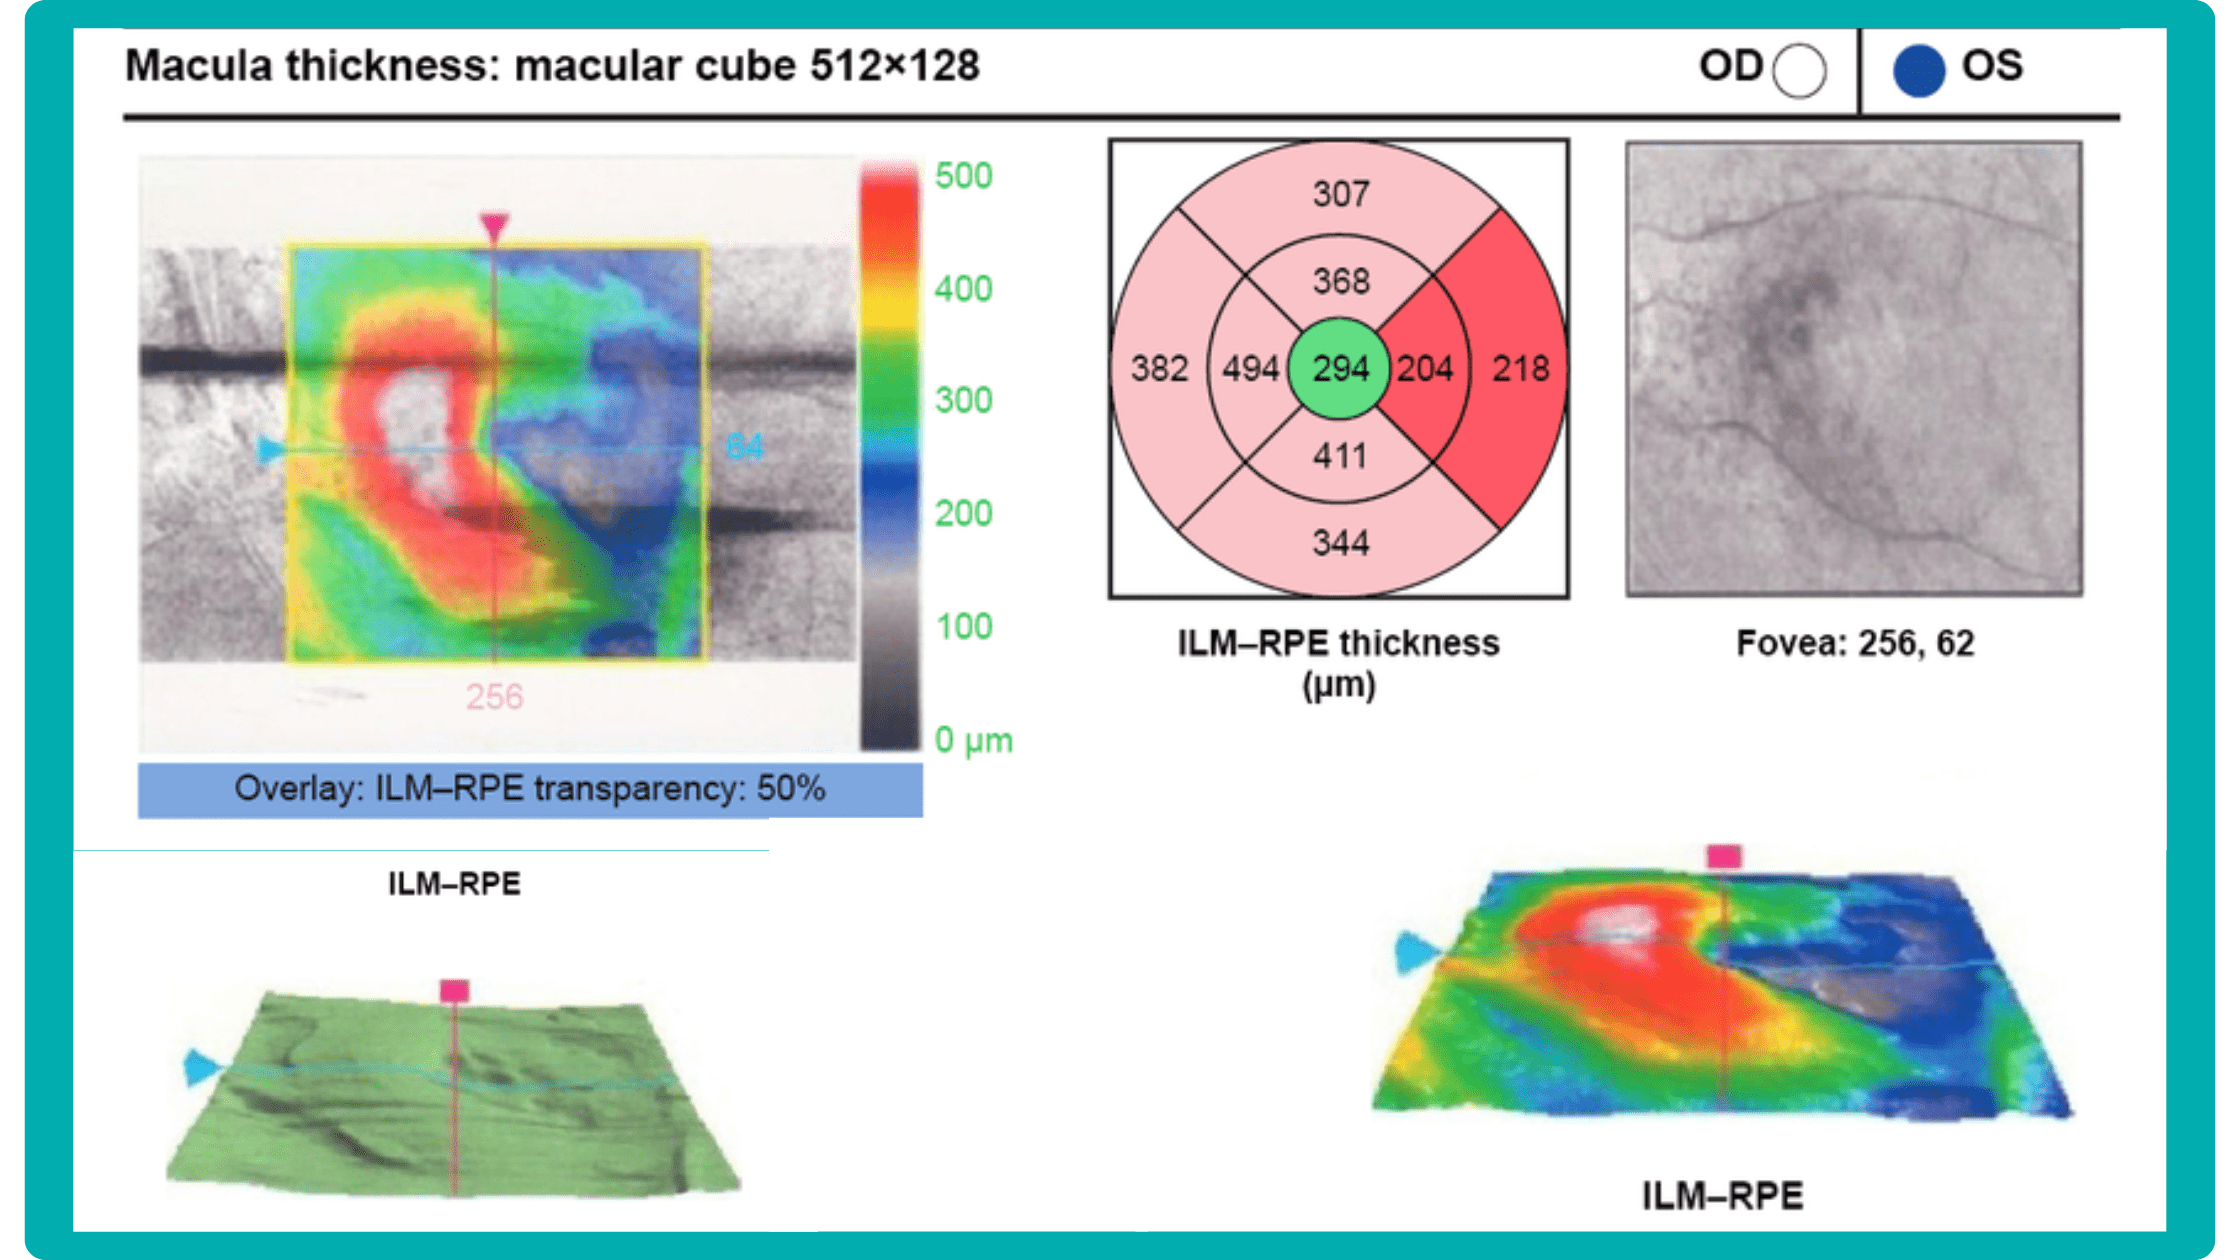

To illustrate the point, here is a handwritten referral compared to one of the types of customised OCT report from the Altris AI system, a platform that automates AI-powered OCT scan analysis for 70+ pathologies and biomarkers. This screenshot, in particular, shows segmented retina layers and highlights biomarkers of Dry AMD alongside a comparison of the patient’s macular thickness over visits.

OCT has become a golden standard for diagnosing and monitoring many ocular pathologies, thanks to its unparalleled level of detail in ophthalmic imaging.

While retinal reports vary among OCT models, they typically include:- a foveally centered B-scan,

- a quantitative thickness map,

- and a semi-quantitative thickness map.

The B-scan offers a visual snapshot of foveal architecture and confirms proper scan centering. The quantitative thickness map employs the ETDRS sector map to measure retinal thickness within a 6mm circle around the fovea, with specific measurements for the foveal sector (1mm), inner macular ring (3mm), and outer macular ring (6mm).

Progression analytics enable comparison of serial macular scans, which is invaluable for managing vitreomacular interface disorders and macular edema. The semi-quantitative thickness map provides a broader overview of retinal thickness throughout the scan.

Given this amount of data, it is challenging to identify subtle and localized retinal pathological changes. As a result, entire OCT datasets are represented by few aggregated values, and the standard OCT reports generated by most devices often rely on significant data reduction to simplify interpretation, which you can usually not customize.

Imaging biomarkers are a particularly attractive option for clinical practice due to their non-invasive and real-time nature. Quantitative measurements of retinal thickness, fluid volume, and other biomarkers relevant to diseases like diabetic retinopathy and age-related macular degeneration aid in treatment monitoring.

OCT reports with customized measurements and selected biomarkers, retinal layers, or segments allow for precise focus on treatment monitoring and patient response to therapy. This personalized approach enhances clinical decision-making by highlighting each case’s most relevant information.

In current clinical practice, macular damage assessment typically involves measuring the distance between the ILM and RPE layers, summarized in a post-scan report.

However, these reports often fall short of visualization best practices, employing ineffective or inconsistent color schemes. Additionally, they lack flexibility, with static visuals preventing in-depth examination of specific details. Despite these limitations, these reports remain valuable for many clinicians by distilling complex data into a manageable format.

Let’s explore how this applies to a clinical case, such as monitoring a patient with Wet AMD during follow-up visits.

Data demonstrates that OCT findings can reveal the onset or progression of neovascular AMD before a patient reports new symptoms or changes in visual acuity. In fact, OCT images are reported to have the best diagnostic accuracy in monitoring nAMD disease states. This underscores the importance of key OCT findings or biomarkers in personalizing anti-VEGF treatment, achieving disease control, and reducing monitoring burdens.

Central Retinal Thickness emerged as one of the earliest OCT biomarkers used as an outcome measure in clinical trials for nAMD.

However, due to confounding factors, CRT’s use in outcome-based assessments of nAMD varies. Thus, it is essential to evaluate additional morphological changes alongside retinal thickness and their relationships with functional outcomes.

It has been reported that OCT images have the best diagnostic accuracy in monitoring nAMD disease states.

Another finding that is correlated with a worsening VA due to the associated photoreceptor defects is any damage to the four outer retina layers, including the RPE, interdigitation zone (IZ), ellipsoid zone (EZ), and external limiting membrane band (ELM).

OCT is a valuable imaging tool for visualizing subretinal hyperreflective material (SHRM). It can automatically identify and quantify SHRM and fluid and pigment epithelial detachment to calculate the overall risk of worsening visual outcomes associated with SHRM.

Subsequent follow-up visits will then display the most relevant picture, highlighting the most pertinent biomarkers for tracking a particular pathology (wet AMD in our example) and comparing their volume, progression, or regression through visits.

Another helpful option is retinal layer segmentation, which focuses solely on the retinal layers of interest for the specific case.

This level of customization empowers clinicians with a comprehensive yet targeted view of the patient’s condition. It saves time from manually detecting anomalies on scans and facilitates informed decision-making and personalized treatment plans.